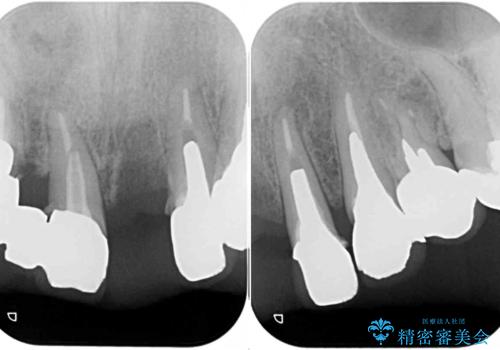

診断をした結果、前医の診断の通り、2本とも破折しており、既に抜去している歯を含めて3本の抜歯が必要な状態でした。

歯の破折による抜歯のため、歯槽骨の欠損が大きく、骨造成処置の併用が必要であり、骨造成が落ち着くまでに半年ほど時間を要することになります。

2本同時に抜去して一時的な入れ歯の使用を提案しましたが、極力固定式の仮歯を使用したいとのことで、半年に1本ずつ埋入することとし、トータルで1年強を要する治療計画となりました。